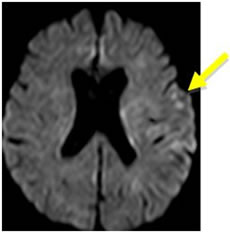

脳梗塞は発症してもすぐにCTやMRIで所見が出るわけではありません。最も感度の良い「拡散強調画像」という特殊な検査法でも、発症から約30分から1時間ほど経たないと異常は発見できません。従って、ごく早期の脳梗塞は「脳卒中の症状があり、CTで出血がなければ脳梗塞」と診断するわけです。また、CTでは診断に限界がある場合も多く、MRI検査が必要です。当院では症状のある患者さんは最優先にMRI検査(24時間稼働)をしております。(図1)

図1:脳梗塞のMRI拡散強調画像。矢印の部位が淡く白くなっています。 |